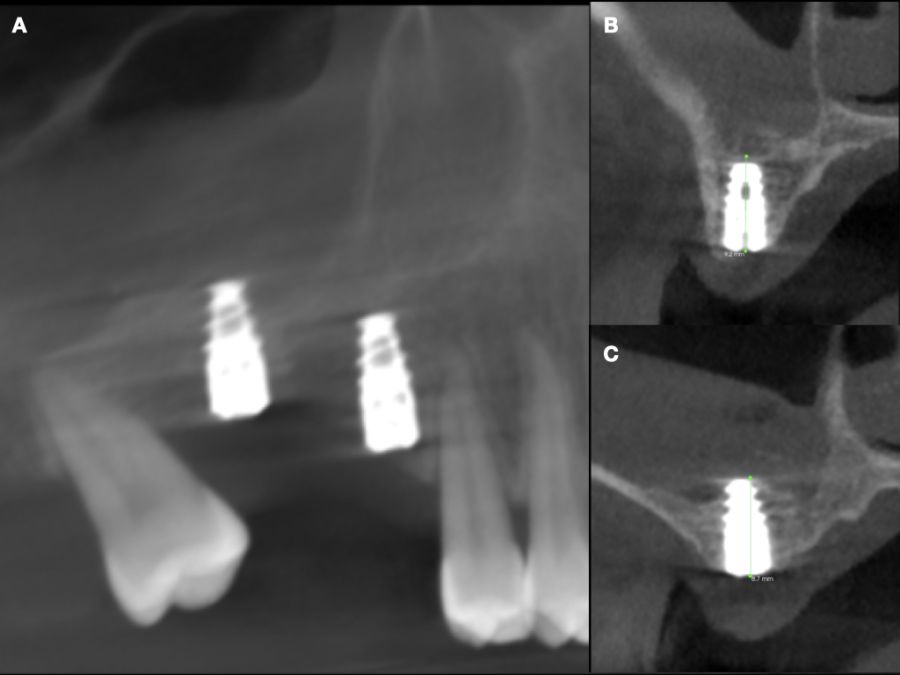

En la historia clínica, no se evidenciaron antecedentes médico-quirúrgicos de interés, alergias medicamentosas conocidas ni hábitos nocivos. A la exploración intraoral, se apreciaron las ausencias de 1.6 y 1.7 y la presencia del 1.8 y 4.8 (Figura 1). En la exploración radiográfica mediante escáner de haz cónico (CBCT) se apreció una altura residual de 5,0 mm en 1.6, donde se podría colocar un implante simultáneo, y de 2,6 mm en la zona del 1.7, dificultando la colocación de un implante de manera simultánea a la elevación de seno de acceso lateral (Figura 2).

Seis meses tras la cirugía de elevación de seno maxilar se realizó la reentrada para la colocación de implantes. Se obtuvo una biopsia de tejido óseo de 3 x 7 mm mediante trefina y se solicitó un análisis histomorfométrico, obteniendo un 30,56% de hueso vital (Figura 7). Tras la muestra para la biopsia se colocaron dos implantes bone level Naturactis de ETK® (ETK Implants S.L, Sant Boi de Llobregat, España) con un torque de inserción de 35 Ncm, comprobándose su correcta colocación en el postoperatorio inmediato mediante una radiografía periapical (Figura 8). Seis meses tras la colocación de los implantes la paciente pudo acudir a realizarse la segunda fase para colocar pilares de cicatrización, y mediante un CBCT de comprobación se valoró la altura ósea final, teniendo un incremento de 4,2 mm en la zona del 1.6, y de 6,1 mm en la zona del 1.7 (Figura 9).